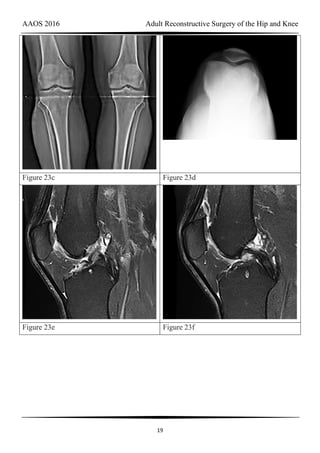

CLINICAL SITUATION FOR QUESTIONS 69 THROUGH 72

Figures 69a through 69c are the radiograph and MR images of a 37-year-old woman who

has had a 2-month history of left hip pain.

Question 69 of 200

Which single symptom and examination finding combination is most likely in this

scenario?

1- Sitting pain with flexion abduction and external rotation of the hip

AAOS 2016 Adult Reconstructive Surgery of the Hip and Knee

57

2- Groin pain and pain with internal rotation and adduction while supine with the hip and

knee flexed 90 degrees

3- Clicking and abductor lurch

4- Buttock pain and pain with hip extension, adduction, and external rotation while prone

PREFERRED RESPONSE: 2- Groin pain and pain with internal rotation and adduction

while supine with the hip and knee flexed 90 degrees

Question 70 of 200

Measurements have been taken on the radiographs shown in Figures 70a through 70d.

Which measurement is abnormal?

1- Head center position

2- Tonnis angle

3- Lateral center edge angle

4- Acetabular inclination

PREFERRED RESPONSE: 3- Lateral center edge angle

Question 71 of 200

Based on the patient’s continued pain, her imitations, the previously noted radiographic

findings, and failure of physical therapy and nonsteroidal anti-inflammatory treatment, what

is the best surgical option?

1- Arthroscopic labral repair

2- Arthroscopy with pincer resection

3- Periacetabular osteotomy (PAO)

4- Hip arthroscopy and PAO

PREFERRED RESPONSE: 1- Arthroscopic labral repair